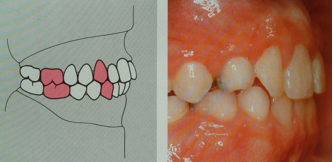

- Alterazioni sul piano sagittale

Si intendono tutte quelle alterazioni in cui un’arcata è troppo avanzata o troppo arretrata rispetto all’altra. Esse vengono classificate in tre classi ortodontiche:

- 1°classe: rapporti antero-posteriori normali

- 2°classe: arcata superiore avanzata rispetto l’inferiore (superiore troppo avanti e/o inferiore troppo indietro )

- 3°classe: arcata superiore arretrata rispetto l’inferiore (superiore troppo indietro e/o inferiore troppo avanti )

Le tre classi ortodontiche posso essere :

-Dentali ovvero legate ai rapporti intercuspidali,classificati secondo Agle.

-Scheletriche ovvero legate ai rapporti tra mascellari secondo misurazioni effettuate sulla radiografia laterale del cranio (teleradiografia ).

La classificazione di Angle prende in considerazione il rapporti del primo molare dei canini

I classe – il primo molare superiore e/o il canino superiore risulta

arretrato di mezza cuspide rispetto al corrispondente inferiore.

II classe – il primo molare superiore e/o il canino superiore risulta avanzato di almeno mezza cuspide rispetto al corrispondente inferiore.

III classe – il primo molare superiore e/o il canino superiore risulta arretrato di almeno mezza cuspide rispetto al corrispondente inferiore.

1^ classe dentale

2^ classe dentale

3^ classe dentale